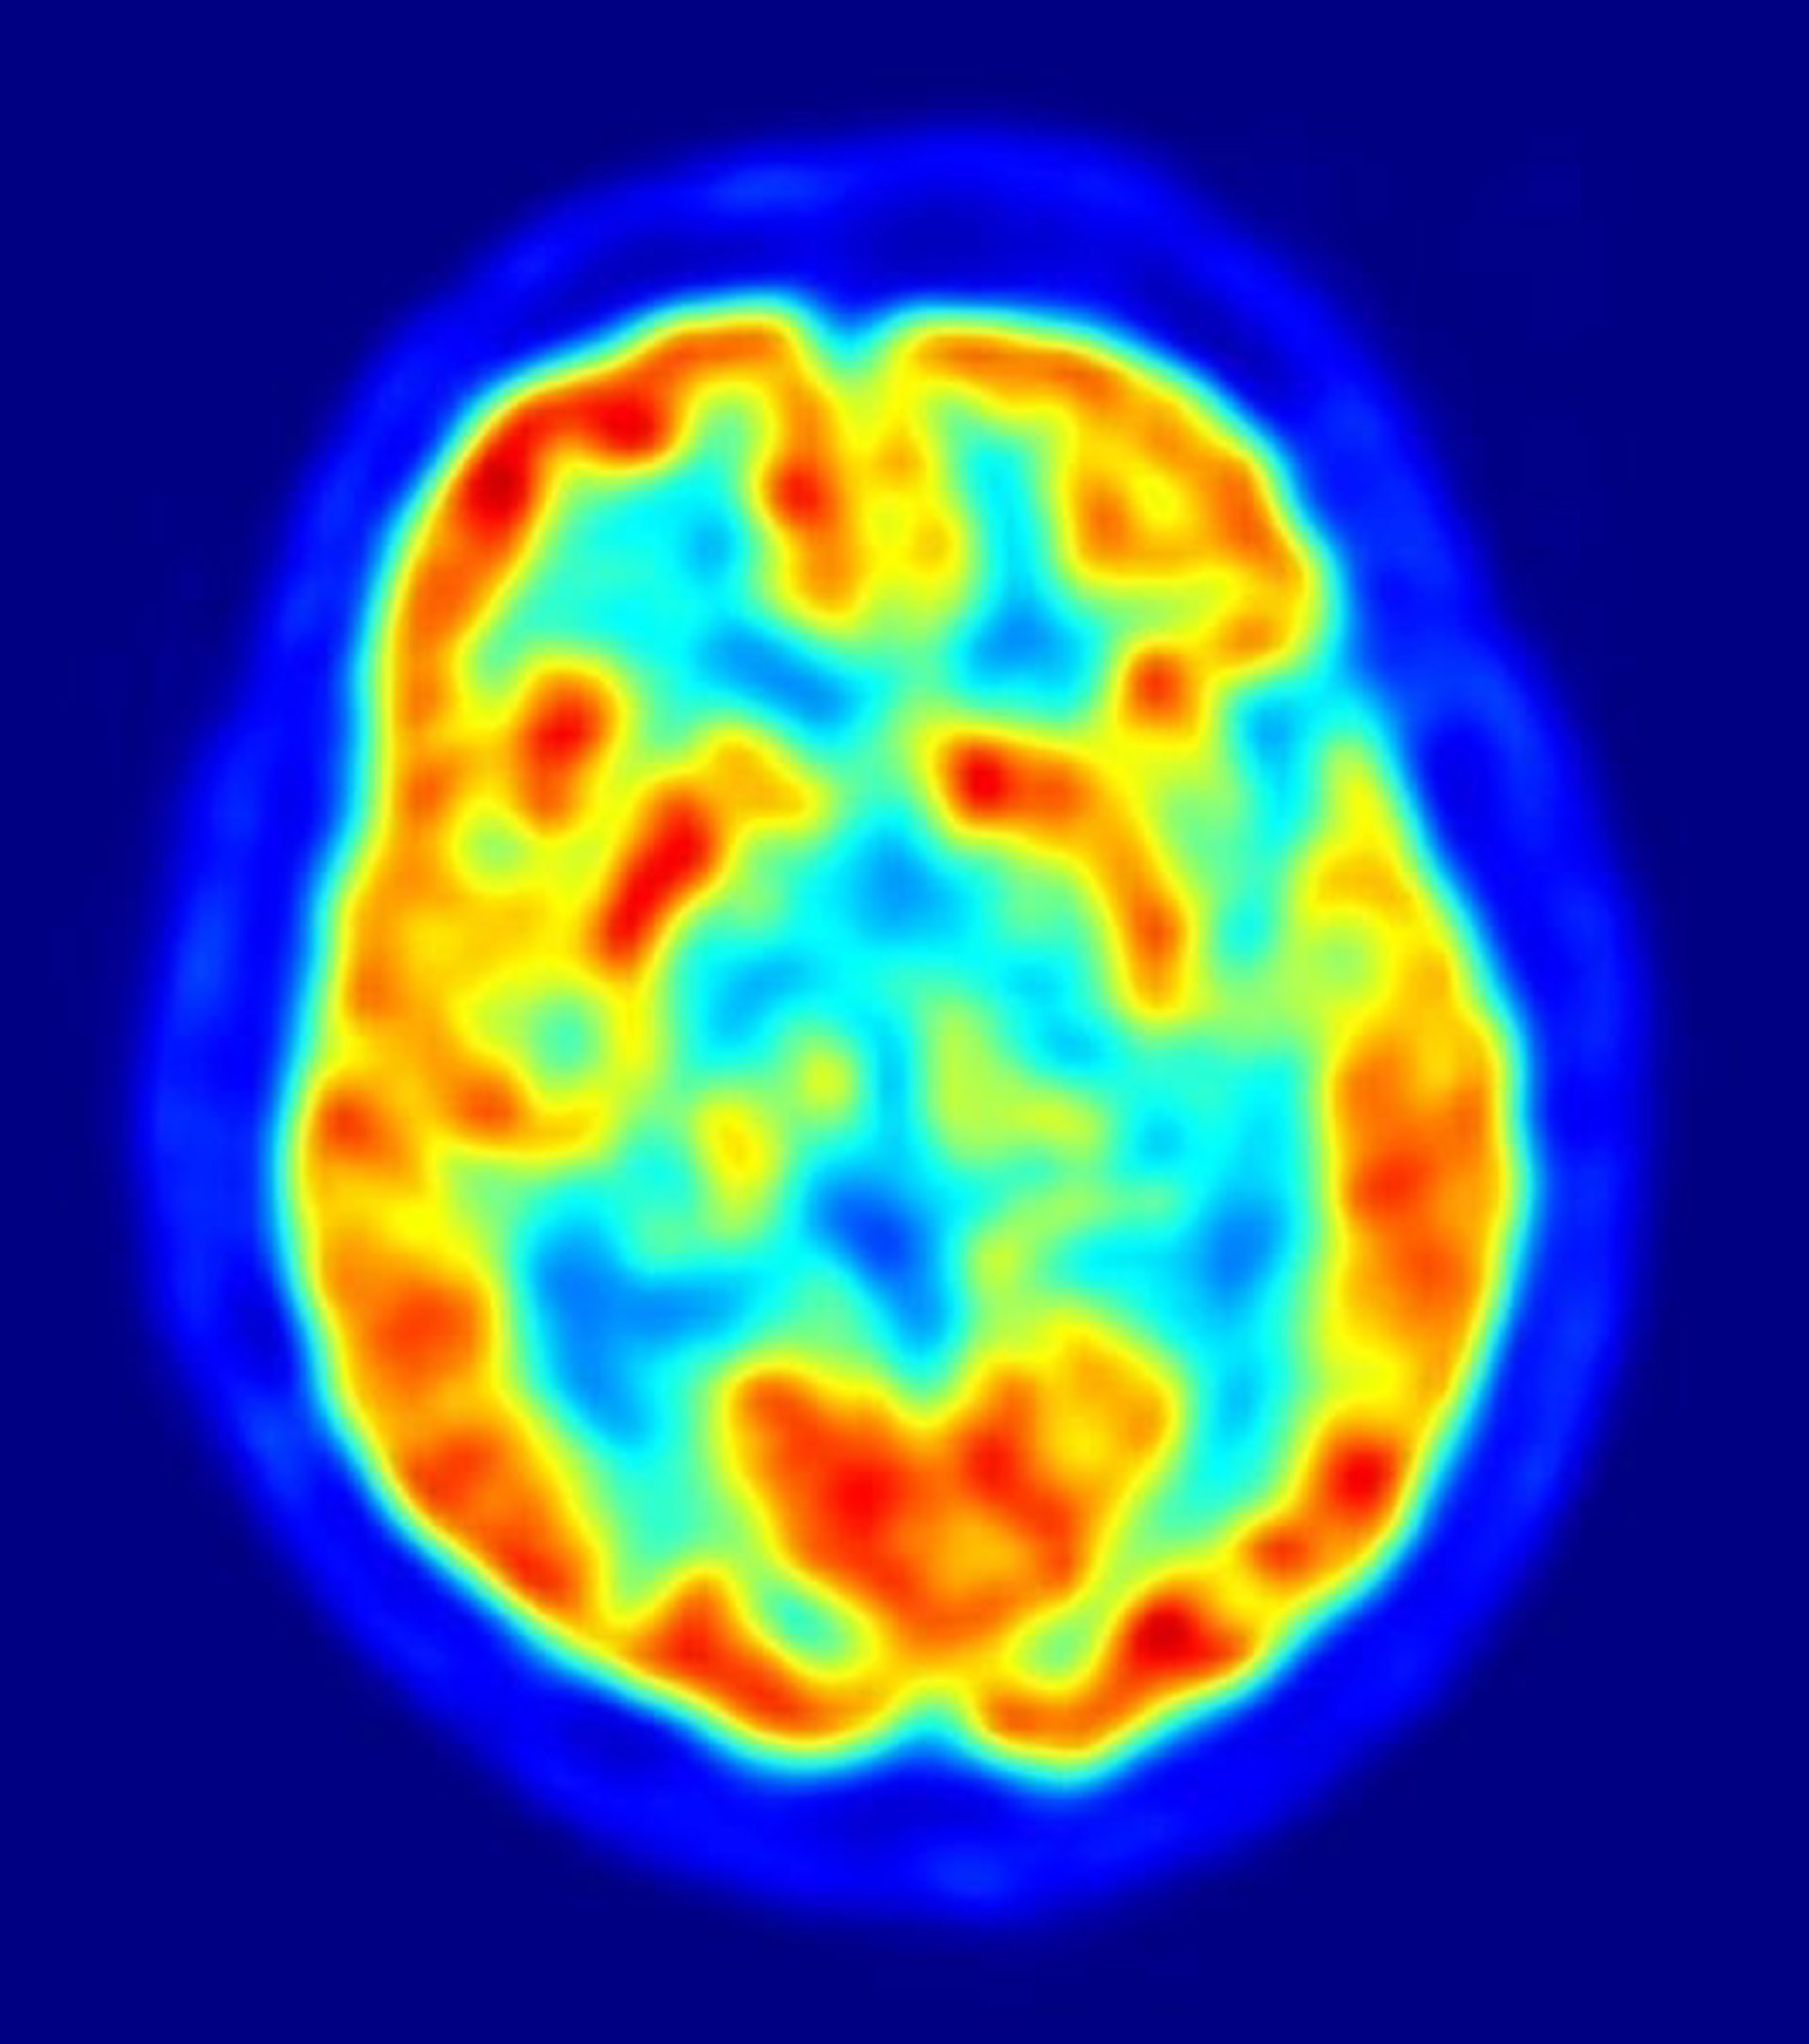

Imagen Escáner Cerebral

Utilizando una resonancia magnética funcional (fMRI, por sus siglas en inglés) y modelos computacionales, los investigadores de Berkeley han tenido éxito decodificando y reconstruyendo experiencias visuales dinámicas, en este caso mientras los sujetos del estudio visionaban 'trailer' de películas de Hollywood.

Nishimoto y otros dos miembros del equipo de investigación sirvieron como sujetos para el experimento, ya que el procedimiento requiere que los voluntarios a permanezcan inmóviles dentro del escáner durante horas. Visionaron dos conjuntos separados de 'trailers' de películas de Hollywood, mientras que la fMRI medía el flujo sanguíneo de la corteza visual --la parte del cerebro que procesa la información visual. En el ordenador, el cerebro se dividió en pequeños cubos tridimensionales conocidos como píxeles volumétricos, o 'voxels'. "Hemos construido un modelo para cada voxel que describe cómo se forma la información del movimiento en la película asignada a la actividad del cerebro", explica Nishimoto.